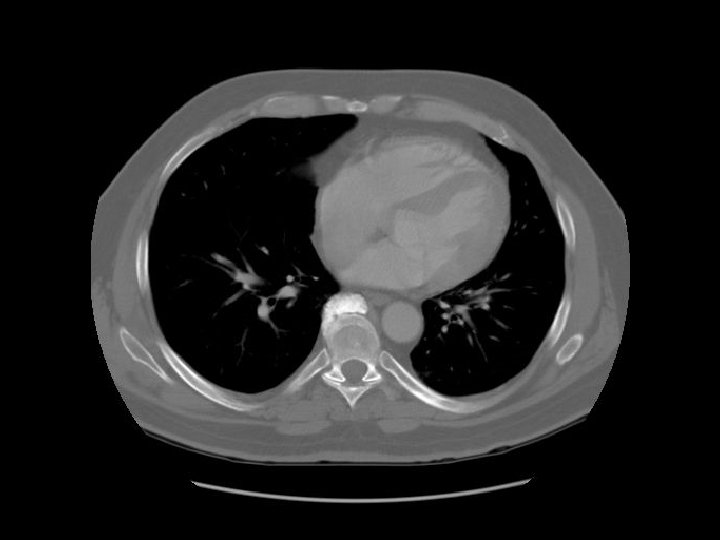

Ascending aorta Main pulmonary artery Descending aorta

Contrast in SVC is diluted by blood from the azygous vein. Esophagus Azygous vein

Left pulmonary artery Carina

Right pulmonary artery Main pulmonary artery RUL bronchus Left pulmonary artery

Left main bronchus

SVC Intermediate bronchus LUL division

Ascending aorta

Rt atrium